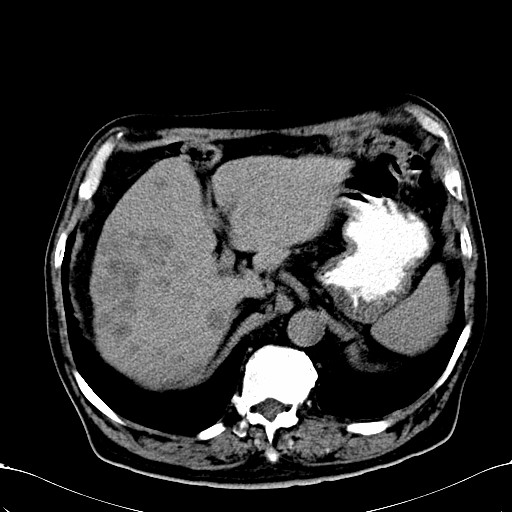

标题: CT28270:胰管扩张,肝多发占位

患者,男,75岁。

肝脏多方低密度结节,边缘模糊,考虑多发转移,胰管明显扩张,建议增强扫描钩突情况

肝脏多发低密度灶,胰头似呈低密度,胰管扩张,建议增强,

胰管显著扩张,但胆总管未见扩张征象,不太符合胰头占位!考虑慢性胰腺炎.胃窦占位并肝内转移可能!mrcp胃镜增强一起上!